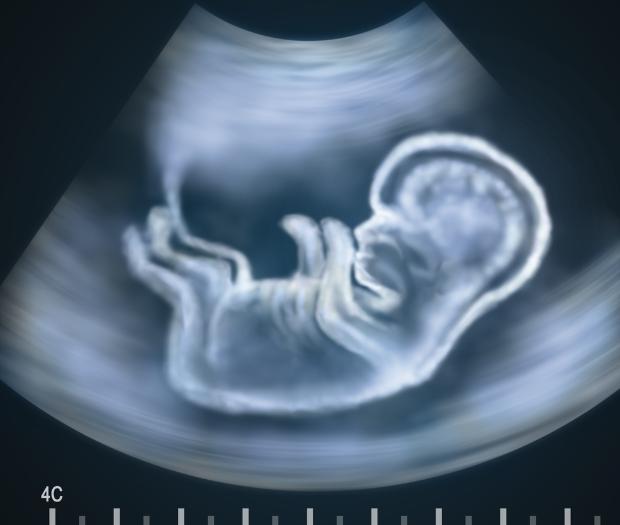

Нов тест засича дали бебето има генетично заболяване още в началото на третия месец от бременността на майка му. Изследването вече се прави и у нас, но цената му е доста солена - 2500 лева.

Чрез теста може да се открие синдромът на Даун, синдромът на Едуардс и синдромът на Патау, които са най-често срещаните генетични заболявания.

Това става още в 9-ата гестационна седмица от бременността. Тестът може с 99% точност да покаже дали едно дете е носител на генетична аномалия. Изследването се прави чрез вземане на кръв от вена на бъдещата майка. Така от нея се изолира ДНК-то на плода. Пробата се изпраща до лаборатория в Германия, където се подлага на високотехнологичен генетичен анализ.

Досегашните методи за определяне на наличие на генетични аномалии включват биохимичен скрининг. Той е неинвазивен и не крие рискове за бременността, но дава около 5% фалшиви положителни резултати и пропуска да улови от 5 до 20% от случаите на синдром на Даун. Инвазивните методи като амниоцентеза и хорионбиопсия дават по-голяма точност, но пък крият риск от спонтанен аборт. При хорионбиопсията този риск е до 5%. Фалшивите положителни резултати при новия пренатален тест са под 0,1%, обясняват специалистите. До края на годината той ще бъде използван и за изследване при многоплодна бременност.